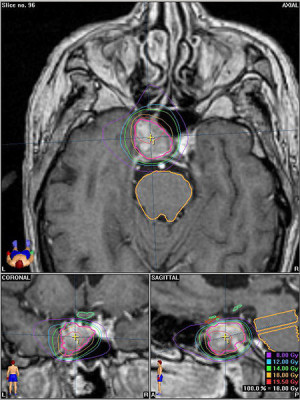

Casos Neuroloquirúrgicos

Envíado por Dr. Ruben Eduardo Amaya Contreras